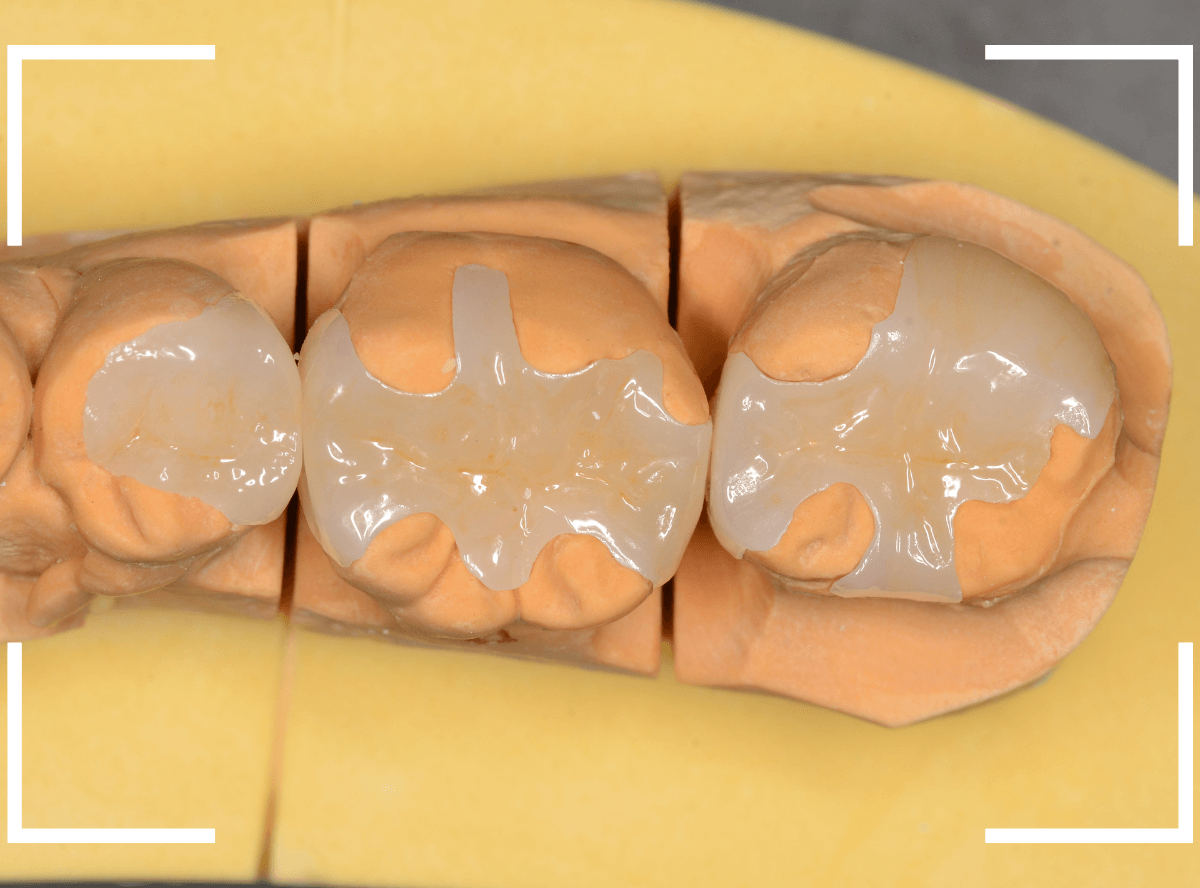

模型上で精密に製作します。

最終setした状態です。

左側の大臼歯2本が、ジルコニア・インレー

右側の小臼歯2本が、E-MAX・インレー

になります。

見た目にほとんど遜色ない仕上がりにできました。

普段あまりしない、4歯連続のインレー治療でしたが、精密に仕上げ・setする事が出来てホッとしました。